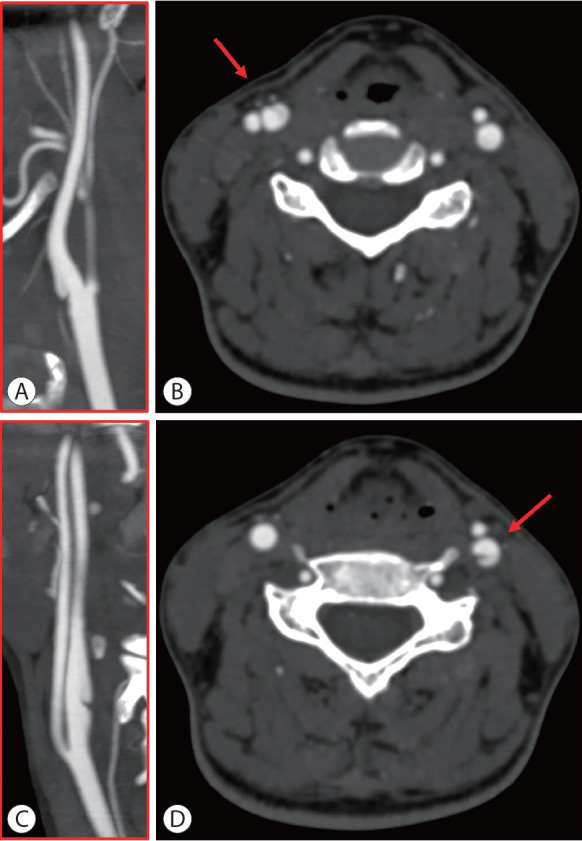

颈动脉网在50多年前被描述为非典型纤维肌肉发育不良(FMD)亚型,并有高度支持的病理证据作为内膜FMD。在接下来的几十年里,从导管血管造影或数字减影血管造影(DSA)到无创成像技术的转变以及病理程序的急剧减少导致了这些信息的逐渐丢失。目前,由于颈动脉网与隐源性缺血性脑卒中的关系,人们对其的关注有所增加。事实上,潜在的假设是颈动脉网的形态特征可能决定了动脉对动脉栓塞的血栓形成潜力。颈动脉网的病理允许识别嵌入在网袋中的小血栓,并且从颅内动脉血管内取出的血栓的特征非常相似。颈动脉网的诊断通常采用非侵入性技术,如计算机断层血管造影、超声和磁共振成像,需要两种不同技术的一致性来确认诊断。在诊断不确定的情况下,当考虑介入治疗缺血性中风或颈动脉网时,通常考虑DSA。有症状病例的治疗选择包括药物治疗(单或双抗血小板)或介入治疗(手术或支架置入术),但没有关于治疗的随机对照试验。本综述的主要目的是介绍目前关于颈动脉网的知识,检索FMD的历史数据和血管造影分类,并讨论在症状病例中与卒中相关的生物学合理性,以及更新FMD分类的必要性,以及前瞻性数据。

Carotid web was described more than 50 years ago as an atypical fibromuscular dysplasia (FMD) subtype with highly supporting pathological evidence as intimal FMD. In the following decades, the transition from catheter angiography or digital subtraction angiography (DSA) to non-invasive imaging techniques and the dramatic decrease in pathological procedures contributed to the gradual loss of this information. Currently, attention on the carotid web has increased due to its association with cryptogenic ischemic stroke. In fact, the underlying hypothesis is that the morphological features of the carotid web may determine a thrombogenic potential with artery-to-artery embolism. The pathology of the carotid web allowed identification of small thrombi embedded in the web pouch, and the features of thrombi endovascularly retrieved from intracranial arteries are very similar. The diagnosis of carotid web is usually made by non-invasive techniques, such as computed tomography angiography, ultrasound, and magnetic resonance imaging, requiring the concordance of two different techniques for confirming the diagnosis. DSA is usually considered in cases of diagnostic uncertainty and when interventional treatment of ischemic stroke or carotid web is considered. Treatment options in symptomatic cases include medical therapy (single or dual antiplatelets) or interventional approach (surgery or stenting), but there are no randomized controlled trials about therapy. The main aim of this review is to present the current knowledge on carotid web, retrieving historical data and angiographic classifications of FMD, as well as to discuss the biological plausibility of the association with stroke in symptomatic cases and the need for an updated classification of FMD, together with prospective data.